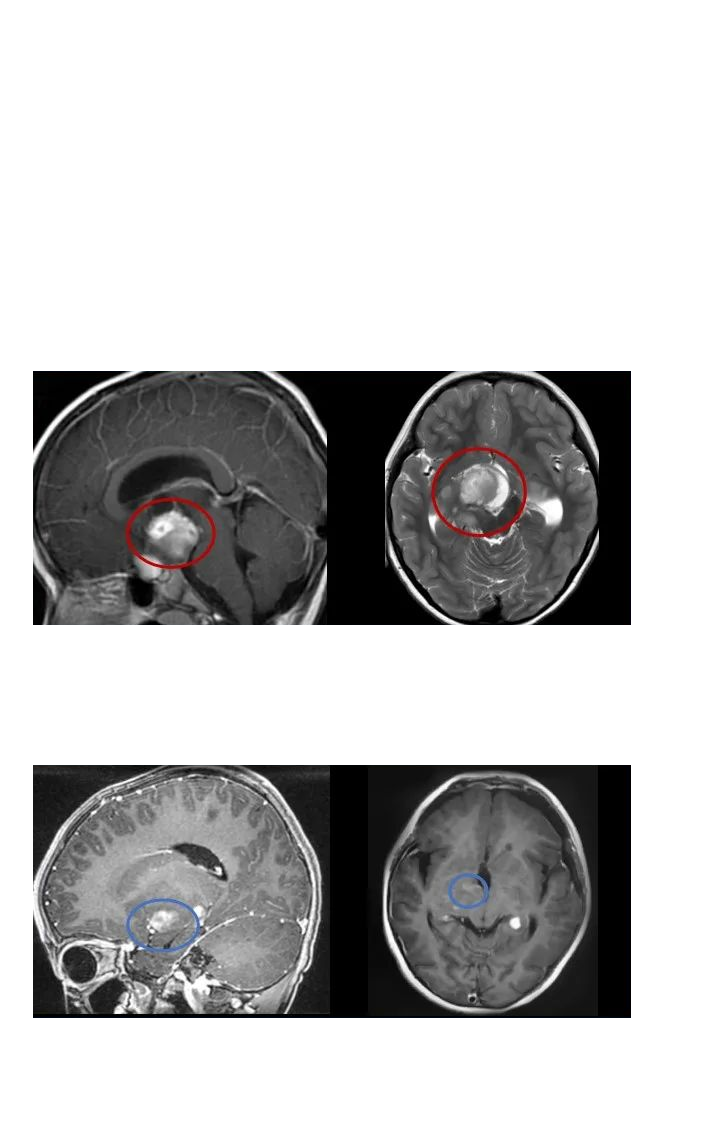

毛细胞型星形细胞瘤

毛细胞型星形细胞瘤,俗称毛星,是一种生长缓慢、边界明显、可伴囊性特点的良性肿瘤,WHOI级,经全切可获治愈,中位生存期达40年,复发几率较低。毛星好发于儿童和年轻人,若肿瘤较小,且病人无临床症状,也可密切随访观察,暂不治疗。当毛星发生于视路(视神经、视交叉、下丘脑)、脑干时,手术难度较大,很多时候甚至被视为不可手术、只能放化疗。

巴教授疑难手术案例:7岁男孩冒疫情赴德国顺利全切

2020年末,6岁的辰辰在遭遇交通事故后,开始出现频繁头晕,就医检查发现小脑占位,提示低级别星形细胞瘤的可能,并且占位所在位置已压迫四脑室和脑干,中线结构局部左移,手术稍有不慎就可能出现瘫痪、长期昏迷等严重后果。

较后,辰辰的父母选择向INC德国巴特朗菲教授寻求咨询意见,教授表示:将尽力全切脑瘤。手术风险低于1-2%,如果确诊为毛细胞型星形细胞瘤,术后复发率将低于2-3%。

2021年初,辰辰由母亲陪护赶赴德国接受教授手术治疗。在术中神经电生理检测护航下,巴教授顺利全切肿瘤,术中无神经损伤,术后辰辰恢复状态很好。

巴教授疑难手术案例:3岁患儿如何摆脱脑瘤、拯救视力?

3岁的康康还没来得及长大看国际,就因患视神经下丘脑胶质瘤面临着失明风险,父母该如何拯救他呢?

由于康康的肿瘤累及视神经、视交叉、视束、视放射、丘脑底垂体轴、三脑室、脑底动脉环等,他出现了视力下降、头痛、呕吐等症状,随之而来的可能还有由内分泌异常引起生长发育异常、认知发育缓慢和心理、行为功能障碍,三脑室的肿块产生阻塞性脑积水等……

幸运的是,康康的父母较后联系到INC国际神经外科医生集团,并咨询成为2021年巴教授来华疑难手术示范的一个病人。在手术中,康康的肿瘤得到了顺利次全切,原有视力得到保留。术后病理结果为毛细胞粘液样型星形细胞瘤,这属于WHO2级胶质瘤,也意味着康康配合术后化疗以及后期的新型放疗可以得到比预期更好的预后。